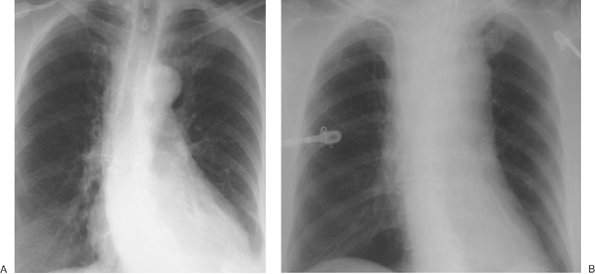

FIGURE 5-1. Left subclavian vein, central venous catheter placement. A: Posteroanterior (PA) chest radiograph shows the catheter entering the left subclavian vein under the left clavicle, crossing the midline as it courses to the right and descending, with the tip positioned over the expected area of the superior vena cava (SVC) (arrow). B: Lateral chest radiograph shows the catheter curving anteriorly (arrow), where it crosses from the left brachiocephalic vein to join the right brachiocephalic vein. This anterior curve makes it possible to determine on a lateral radiograph that a catheter has been placed from the left side.

FIGURE 5-2. Azygos vein placement of central venous catheter. A: PA chest radiograph shows that the catheter tip is positioned over the expected area of the SVC. The tip is seen on end (arrow), however, which is a clue to azygos vein placement. The SVC is joined by the azygos vein posteriorly. B: Lateral chest radiograph shows the catheter coursing posteriorly, along the expected course of the azygos vein (arrows). Note how the more proximal portion of the catheter curves anteriorly (arrowhead), confirming placement from the left.